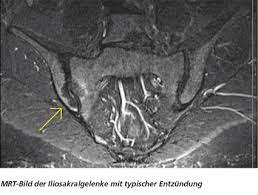

Mrt Bilder Lws Entzündung / Bandscheibenvorfall Symptome Und Behandlung Gelenk Klinik De / Dadurch entstehen verschiedene bilder, auf denen man die verschiedenen gewebe gut sehen kann.. Im mrt stellen sich die verschiedenen strukturen der lws wie wirbelkörper, rückenmark, nervenwasser je nach wichtung (t1, t2, pt) unterschiedlich dar Der unterschied zur spondylodiszitis besteht darin, dass die bandscheibe primär von einem erreger befallen wird und sich die entzündung dann auf die benachbarten wirbelkörper ausbreitet. Die mrt ist die untersuchungsmethode der ersten wahl zur abklärung einer erkrankung an der halswirbelsäule. Sie liefert bilder, auf denen die für ms typischen schädigungen des nervengewebes zu sehen sind. Manchmal können derartige radiologisch nachweisbare veränderungen aber auch fehlen.

Allerdings haben sie eine venenverengung. Mrt der lws t2 (linkes bild) weiß kann man die entzündung der lendenwirbelsäule erkennen, da die bandscheibe durch die fehlstellung aufgebraucht wurde und nun knochen auf knochen reibt und eine entzündung des knochens entsteht. Die entzündung greift hierbei sekundär auf die bandscheibe über. Ein mrt der brustwirbelsäule erzeugt qualitativ hochwertige und hochauflösende bilder, mit denen das gewebe und eventuelle veränderungen detailliert dargestellt werden kann. Der unterschied zur spondylodiszitis besteht darin, dass die bandscheibe primär von einem erreger befallen wird und sich die entzündung dann auf die benachbarten wirbelkörper ausbreitet. Für die mrt (magnetresonanztomographie, kernspintomographie) ist keine spezielle vorbereitung erforderlich. Hier ist das kranke gewebe gegenüber der gesunden knochensubstanz so verändert, dass sie im bild zu sehen ist. Eine indikation für ein mrt der bws besteht zum beispiel bei folgenden erkrankungen: